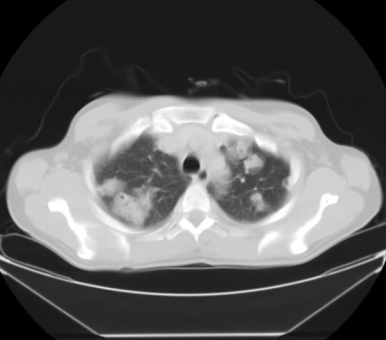

§ Multiple cavitary lesions / nodules (다발 공동성 결절)

- 다발 공동성 병변은 주로 혈관계 전파로 인해 발생한다

- Septic emboli

- Vasculitis : ex) Wegener granulomatosis

- Metastasis :ex) SCC, uterine carcionsarcoma